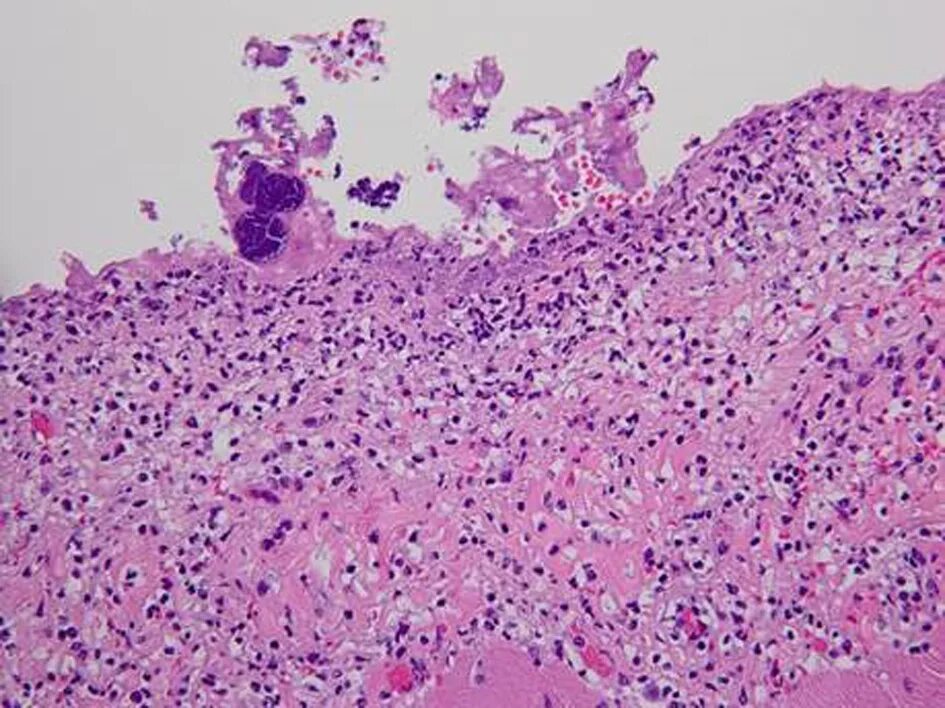

Гистологические заболевания